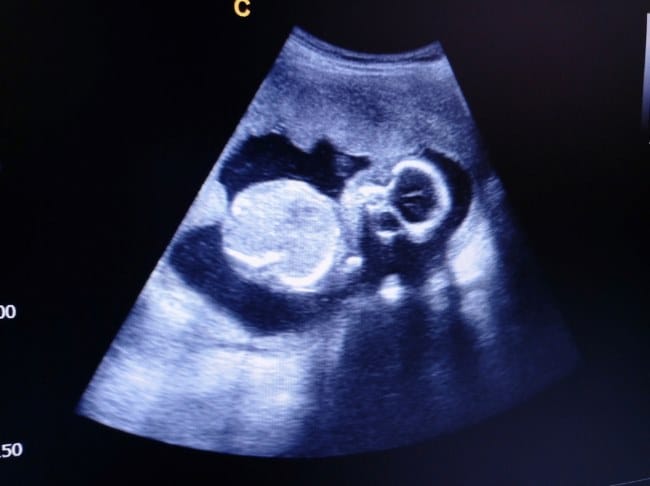

Pada usia kehamilan ini, janin biasanya memiliki panjang sekitar 15–17 cm dan berat sekitar 200–250 gram. Pertumbuhan fisiknya cukup pesat sehingga ruang di dalam rahim mulai terasa lebih sempit. Oleh karena itu, gerakan janin akan lebih mudah terasa, terutama saat Bunda sedang beristirahat atau dalam posisi tenang.

Janin berusia 19 minggu memiliki detak jantung yang sangat cepat, yakni sekitar 130–160 kali per menit, jauh lebih cepat dibandingkan detak jantung orang dewasa. Pada tahap ini, fungsi jantung juga semakin kuat dalam memompa darah ke seluruh tubuh janin, membantu perkembangan organ-organ lainnya.